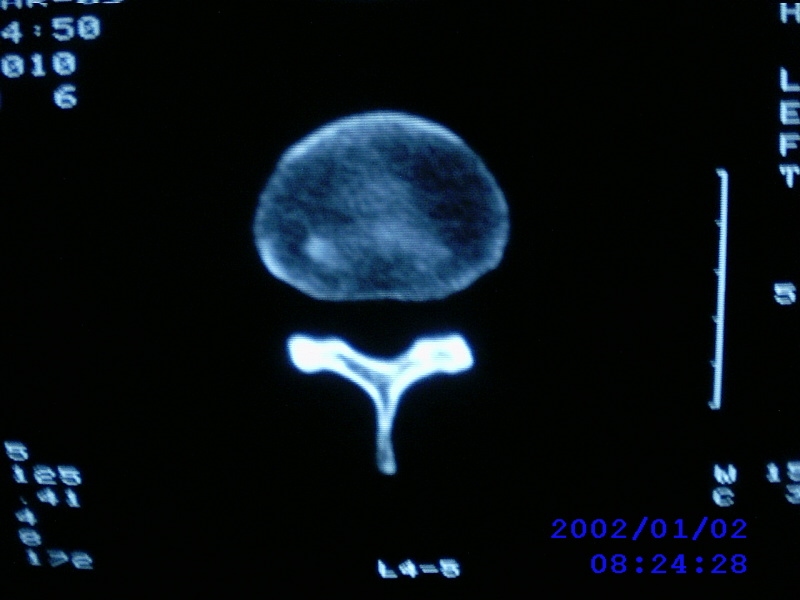

患者,男性,40岁,腰痛伴左下肢疼痛、麻木6年。5年前做过腰椎间盘手术,具体是哪个位置病人记不清了。

我拍的是l4-5、l5-s1

1)l4/5及l5/s1左侧椎板术后改变。2)l5/s1椎间盘突出,l5椎体下缘许莫氏结节。3)l4/5椎间盘膨出并突出。4)l3/4椎间盘膨出。

1)l4/5及l5/s1左侧椎板术后改变。2)l5/s1椎间盘突出,l5椎体下缘许莫氏结节。3)l4/5椎间盘膨出并突出。

1)l4/5及l5/s1左侧椎板术后改变。2)l5/s1椎间盘突出,l5椎体下缘许莫氏结节。3)l4/5椎间盘膨出并突出。4)l3/4椎间盘膨出。支持!